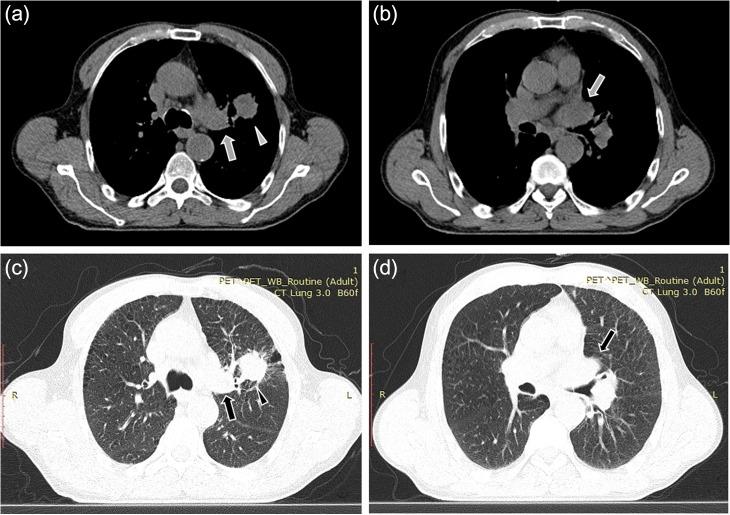

A 61-year-old man presented with dyspnea, left thoracic pain and productive cough. Chest computed tomography demonstrated a solid mass of the left upper lobe, 2.9 × 1.8 cm in size, which had irregular borders and appeared to infiltrate and totally occlude the upper left pulmonary vein extending up to the left atrium (LA) with thrombus formation. The patient underwent median sternotomy and left pneumonectomy, combined with LA thrombus resection under cardiopulmonary bypass (CPB) with bicaval cannulation. The LA was partially resected and the intracavitary thrombus was completely removed. The surgical margins were free of tumor cells. Episodes of embolism were not observed during surgery. The patient was successfully weaned from CPB. The postoperative course was uncomplicated. Pathological examination of the resected specimen revealed giant cell carcinoma.

一名61岁男性患者出现呼吸困难、左胸痛和咳痰。胸部计算机断层扫描显示左肺上叶有一个实性肿块,大小为2.9×1.8厘米,边界不规则,似乎浸润并完全阻塞了左上肺静脉,血栓形成一直延伸至左心房(LA)。患者接受了正中胸骨切开术和左肺切除术,并在体外循环(CPB)双腔插管下联合进行左心房血栓切除术。左心房部分切除,腔内血栓完全清除。手术切缘无肿瘤细胞。手术期间未观察到栓塞事件。患者成功脱离体外循环。术后过程无并发症。切除标本的病理检查显示为巨细胞癌。